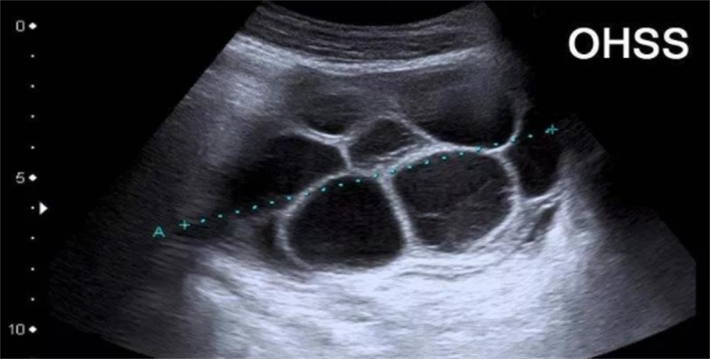

OHSS是人体对促排卵药产生的过度反应,以卵巢囊性增大、毛细血管通透性增加、体液向第三间隙流失为主要特征,根据病情轻重可分为轻度、中度、重度及危重四级。OHSS的高危人群,主要为这几类:年龄<35岁、身体质量指数(BMI)偏低者;多囊卵巢综合征(PCOS)患者;抗缪勒管激素(AMH)>3ng/ml、窦卵泡数(AFC)>15个的卵巢高反应者;既往有OHSS病史者;使用HCG促排卵或维持妊娠黄体者。这些人群在促排过程中,卵巢对促排卵药物敏感性极高,若方案不当,极易引发过度刺激,因此需要更精准、更具针对性的诊疗干预。

在促排过程中,马来西亚专家建立了全程监测机制,通过高精度B超实时监测卵泡发育数量、大小,同时定期检测女性的雌二醇水平,可精准把控卵泡发育节奏。一旦发现卵泡数量过多、雌二醇水平骤升(超过10980pmol/L)等OHSS预警信号,专家会立即调整方案,如暂停促排药,待指标恢复正常后再触发排卵。若风险较高,会果断采用全胚冷冻策略,取消鲜胚移植,待女性身体恢复后再进行冻胚移植,从根本上杜绝OHSS的发生。